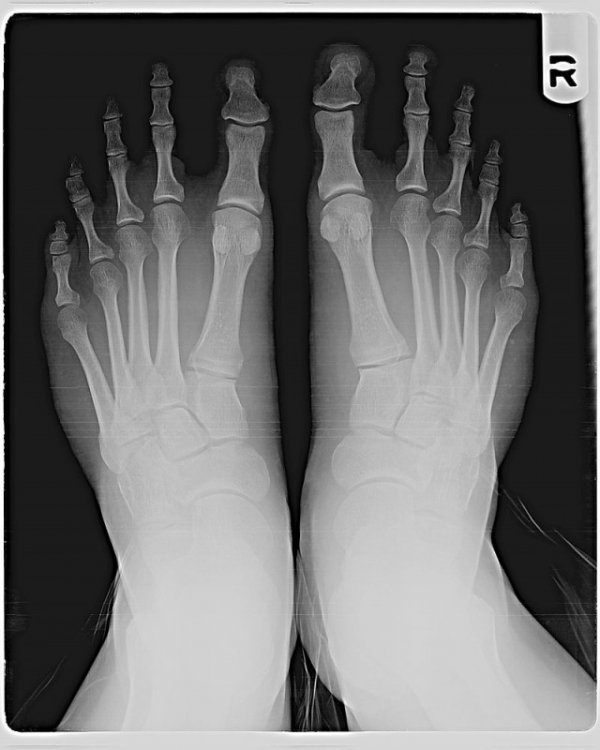

Rendgenski snimak.